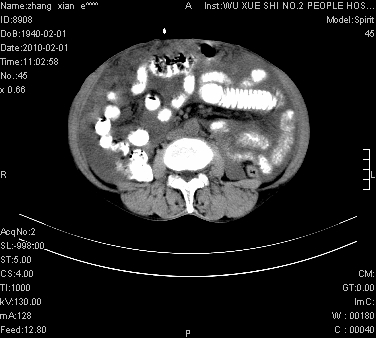

标题: CT24434:70岁 女 腹胀,腹水原因待查 [打印本页]

标题: CT24434:70岁 女 腹胀,腹水原因待查

大量腹水,脾脏囊性占位,子宫颈占位,右侧腹股沟淋巴结肿大,建议+c,先查妇科。

腹盆腔大量积液,子宫增大,子宫颈增大外形不规则,内见低密度影,膀胱后壁显示不清,右腹股沟肿大淋巴结,脾脏囊性占位,子宫颈占位,子宫颈癌?建议增强。

考虑:1、腹膜转移,大量腹水;

2、脾占位性病变;

3、左侧卵巢占位性病变,建议增强进一步检查。

腹盆腔大量积液,子宫增大,子宫颈增大外形不规则,内见低密度影,膀胱后壁显示不清,右腹股沟肿大淋巴结,脾脏囊性占位,子宫颈占位,子宫颈癌?建议增强。支持!